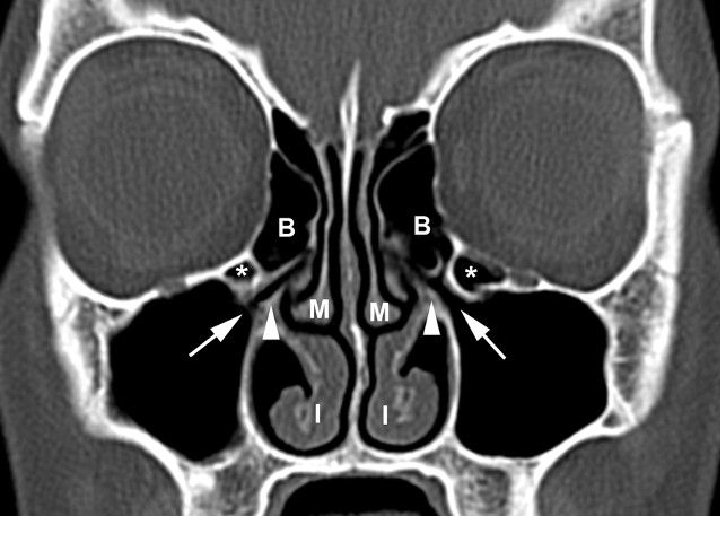

• Lateral wall is marked by three bony projections called turbinates or conchae • superior (part of ethmoid), • middle (part of ethmoid), • inferior (separate bone).

• Sometimes a fourth turbinate concha suprema may also be present. • Below and lateral to each turbinate is a corresponding meatus

• Inferior meatus- nasolacrimal duct opens in its anterior part. • Middle meatus- consists of bulla ethmoidalis, hiatus semilunaris, infundibulum. • Frontal, maxillary and anterior ethmoidal sinuses open into middle meatus.

• Superior meatus- posterior ethmoidal sinuses open into it. • Sphenoethmoidal recess- triangular fossa above the superior meatus. Sphenoidal sinus opens into it.

• OSTEOMEATAL COMPLEX • The middle meatus is the space below and lateral to the middle turbinate, and is often functionally referred to as the osteomeatal complex. • It contains the drainage pathways for the anterior ethmoids, the maxillary and the frontal sinuses.

• The middle meatus is the area that is most commonly involved in the pathophysiology of chronic rhinosinusitis.

• Bulla ethmoidalis • one of the most constant and largest of the anterior ethmoid air cells. • Hiatus semilunaris- hiatus semilunaris is a crescent shaped gap between the posterior free margin of the uncinate process and the anterior wall of the ethmoid bulla

• Ethmoidal infundibulum – • funnel-shaped passage through which the secretions from various anterior ethmoid cells, the maxillary sinus, and, in some cases, the frontal sinus are transported or channeled into the middle meatus.